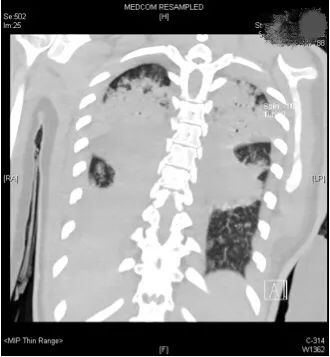

经过专家全面评估后,结果不容乐观,呼吸机的支持水平要求很高,100%纯氧条件下小文体内的氧分压才勉强达标,持续高烧超过40摄氏度,CT复查提示两肺几乎全部实变,炎症指标非常高。

58fb3fc374e44e8d67914c3dbab64164.jpg

小文的影像检查